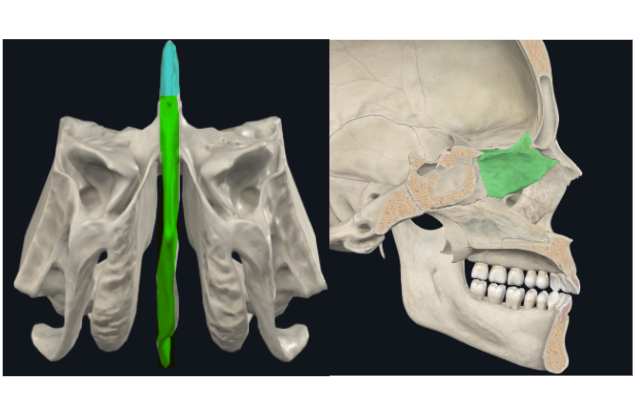

Lámina vertical del etmoides

Lámina perpendicular del etmoides

Forma parte del tabique de separación de ambas fosas nasales (septum/tabique nasal)

Apófisis crista galli por arriba de la lámina horizontal

Apófisis crista galli

Triangular, borde anterior bajo articula con el hueso frontal y completan el agujero ciego(foramen cecum) entre surcos

Lámina cribosa del etmoides

Forma parte del piso de la fosa craneal anterior

Perforada por múltiples orificios, por eso el nombre de cribiforme

Dos apófisis alares que articulan con el frontal, creando el foramen cecum

Foramen Caecum

Llamado también Agujero Ciego

Lámina papirácea en cara lateral

Lámina papirácea del etmoides

Cara orbitaria del etmoides

Lámina delgada y lisa, frágil como un PAPIRO!

Forma una gran parte de la pared medial de la órbita